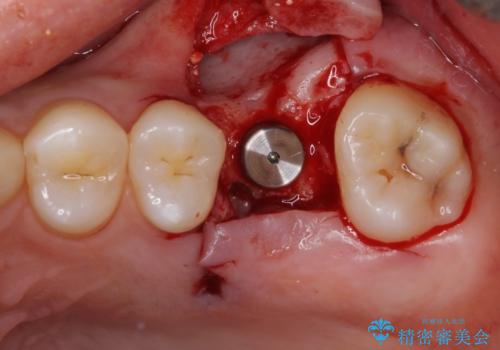

奥歯の虫歯は抜歯が必要であったので、矯正治療前に抜歯をし、矯正治療と並行してインプラントによる補綴治療を行うこととしました。

当院の特徴は、矯正治療とインプラント補綴治療の担当医が同じ歯科医師であるため、両方の治療を並行して行うことができます。